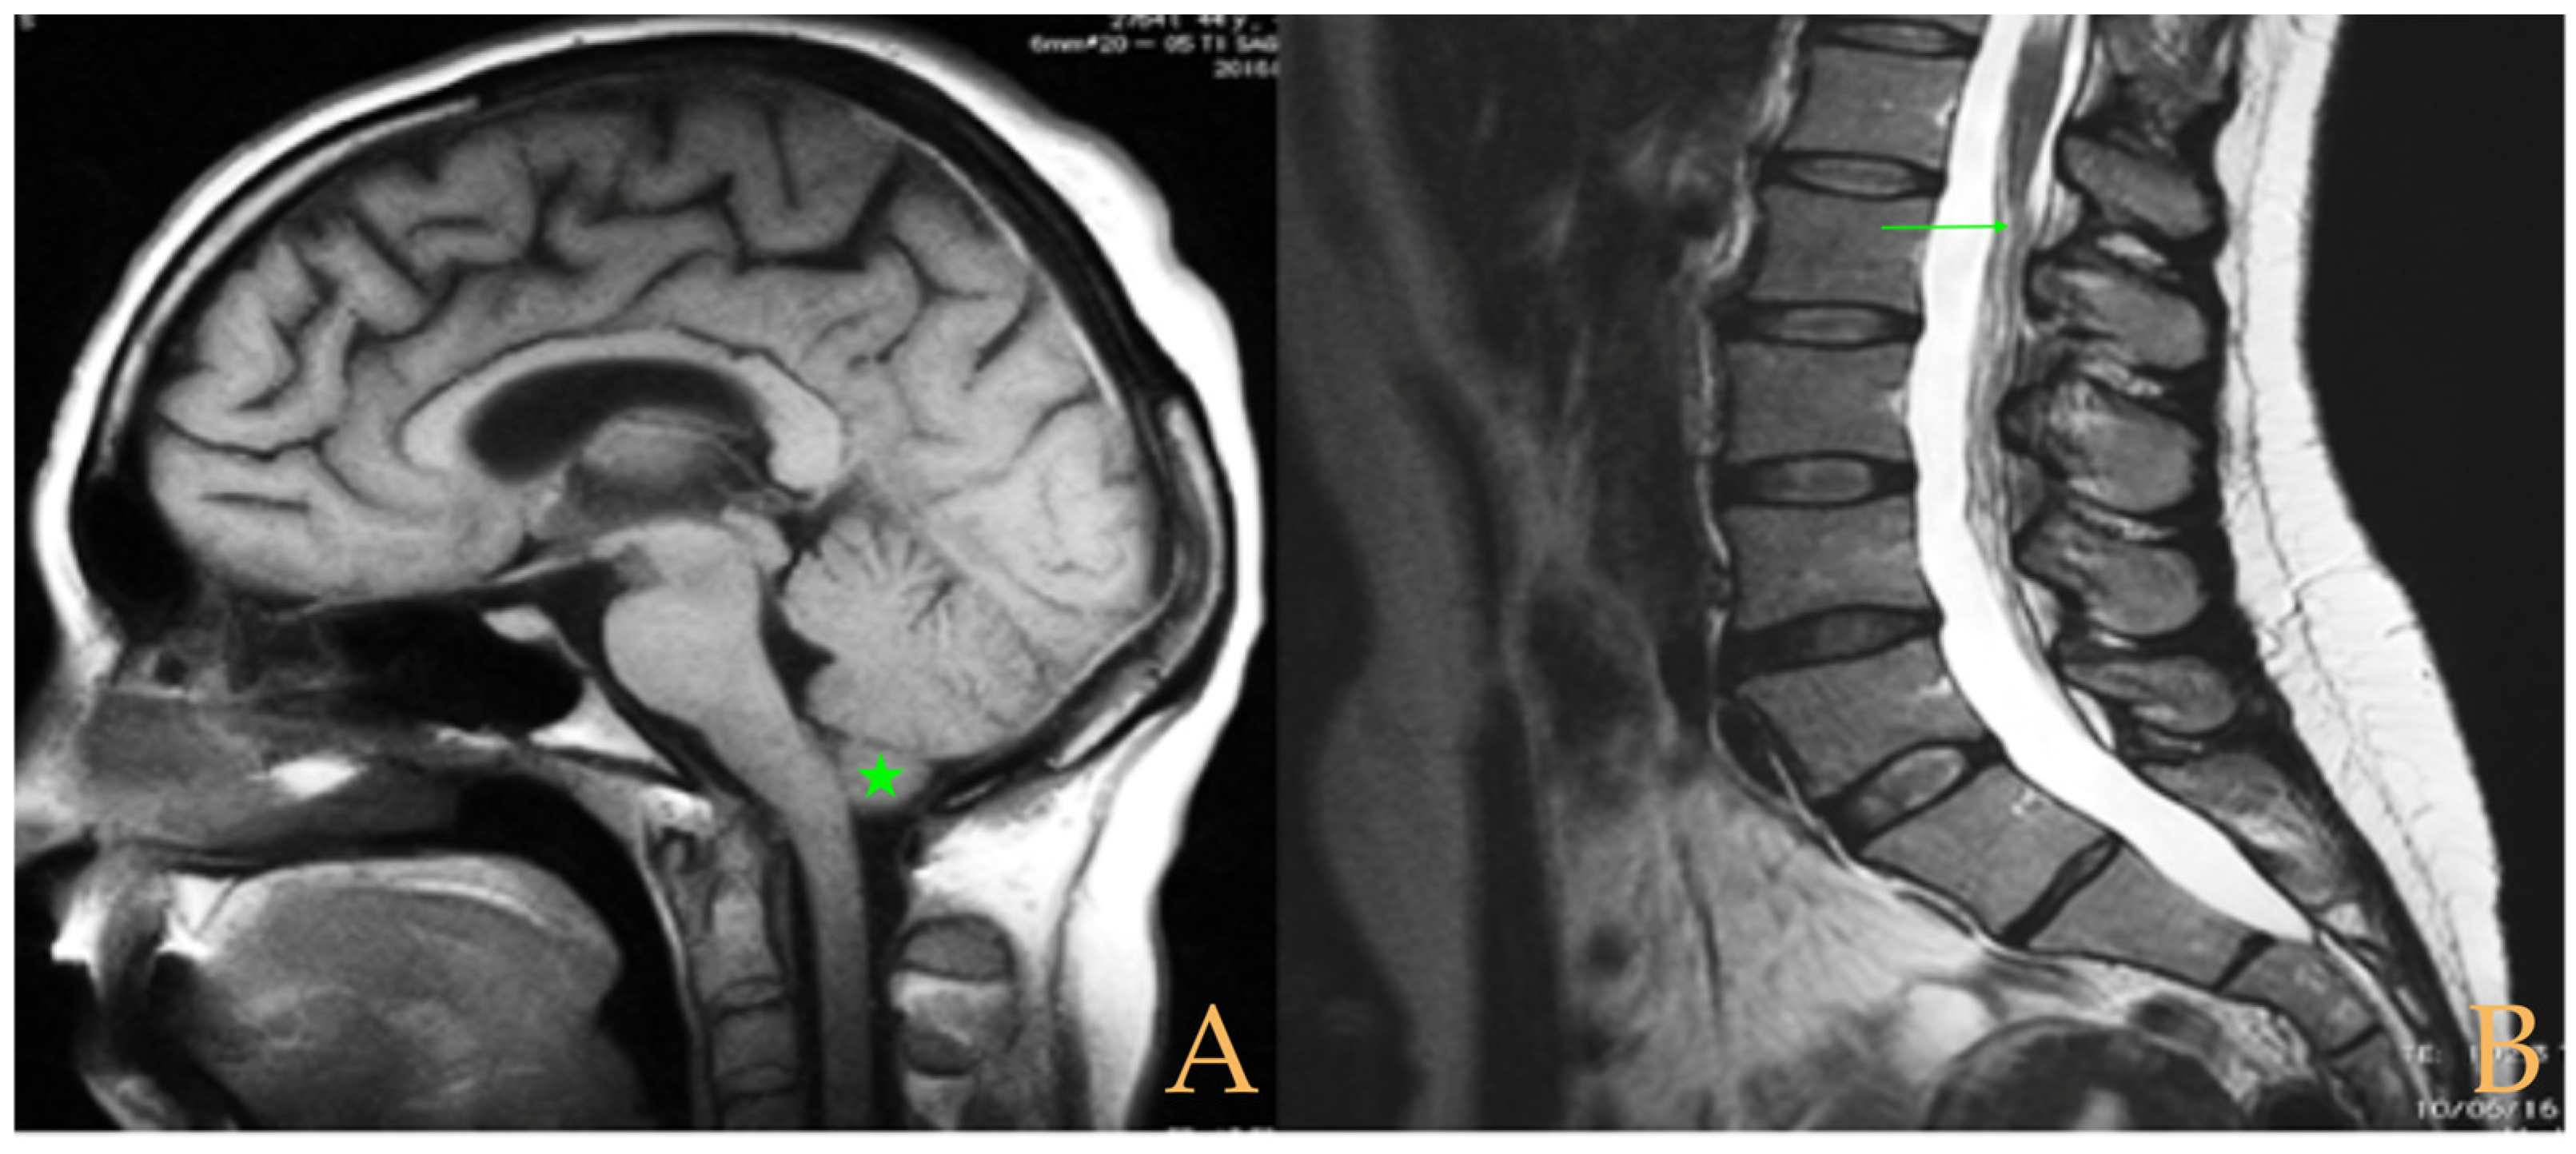

Magnetic resonance imaging showed a slight descent of the cerebellar tonsils, multiple diseased discs, and conus medullaris at the level of the middle third of the L1 vertebra. The X-ray images of the entire spine revealed a mild dextroconvex thoraco-lumbar scoliosis with 5° Cobb angle (Figure 1).

Figure 1.

Imaging of patient 1. A: Mild descent of the cerebellar tonsils (arrows); B: multiple disc disease (arrows) and straightening of the cervical spine (interrupted line); C: conus medullaris at the middle third of L1 (arrow); and D: mild deviation of the vertebral column (interrupted lines).